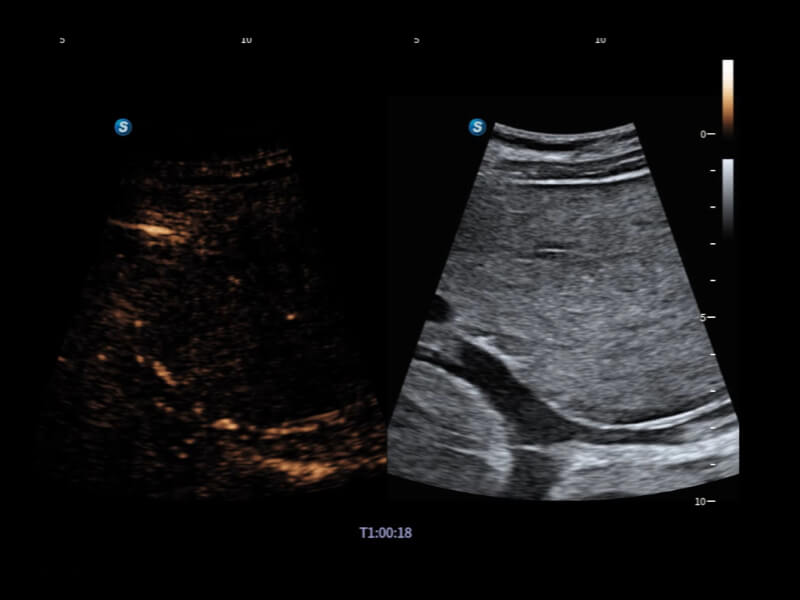

豐富的血流動(dòng)力學(xué)檢測(cè)技術(shù),可在不同醫(yī)療場(chǎng)景中高效捕捉血流信號(hào),助力臨床診療。

在傳統(tǒng)血流的基礎(chǔ)上優(yōu)化掃查和算法策略,能夠更好的抑制組織信息,提煉紅細(xì)胞運(yùn)動(dòng)信息,得到更高幀頻,高靈敏度和分辨率的血流信號(hào),還原更真實(shí)的血流動(dòng)力學(xué)。